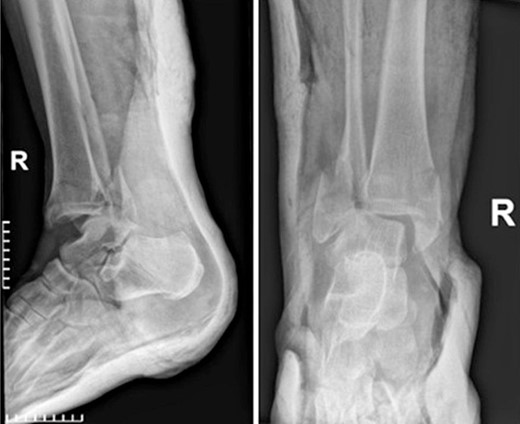

Four doses of i.v. cefoxitin (2000 mg 5 minutes prior to skin incision in the operating room and 1000 mg three times postoperatively every 8 h) were administrated as chemoprophylaxis. The postoperative period was well-progressed, and the patient was discharged on the second postoperative day with a cast and instructions against weight-bearing. In the seventh postoperative week, the patient deviated from the prescribed postoperative regimen by prematurely initiating weight-bearing activities, contrary to the surgeon’s explicit recommendations. During the regular 8-week follow-up, we observed after the radiological evaluation that the syndesmotic screw was broken. This necessitated us to remove the screw and replace it with a 3.5-mm cortical screw (Fig. 3).

Anteroposterior and lateral X-ray of the ankle joint showing the broken syndesmotic screw and the replacement with a 3.5-mm cortical screw on the lateral malleolus 8 weeks after the initial surgery.